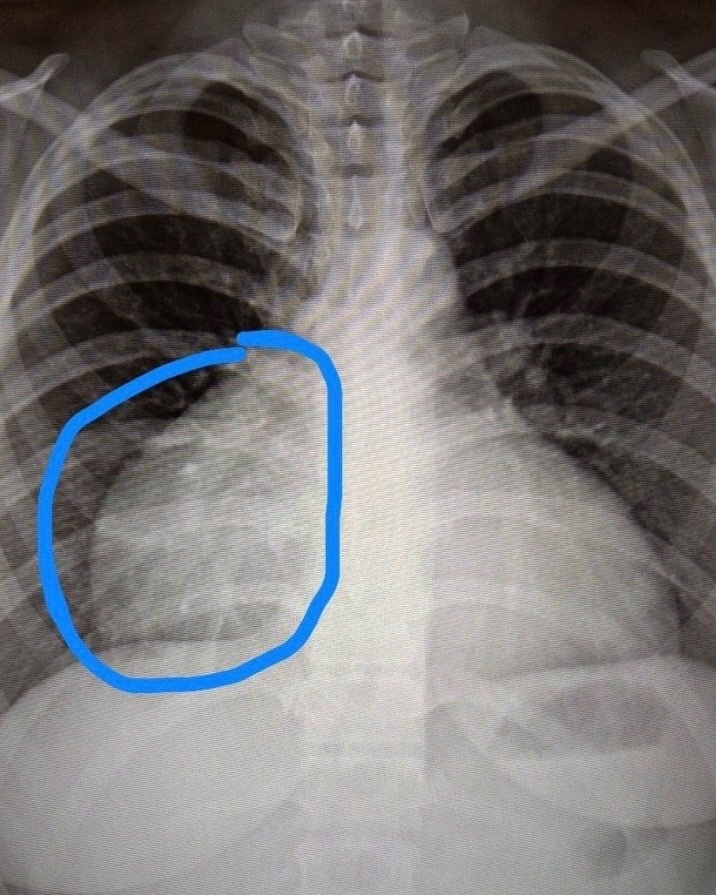

Рентгеновские снимки тератомы средостения: Диагностика и лечение

Раздел: Фотоэссе